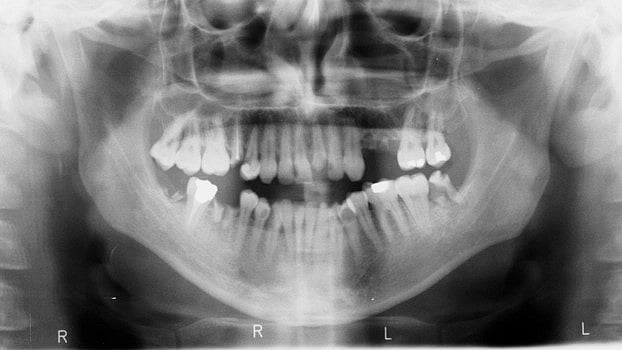

Wisdom tooth and what problems does it cause when not erupted properly. Freeimages

Wisdom tooth and what problems does it cause when not erupted properly.